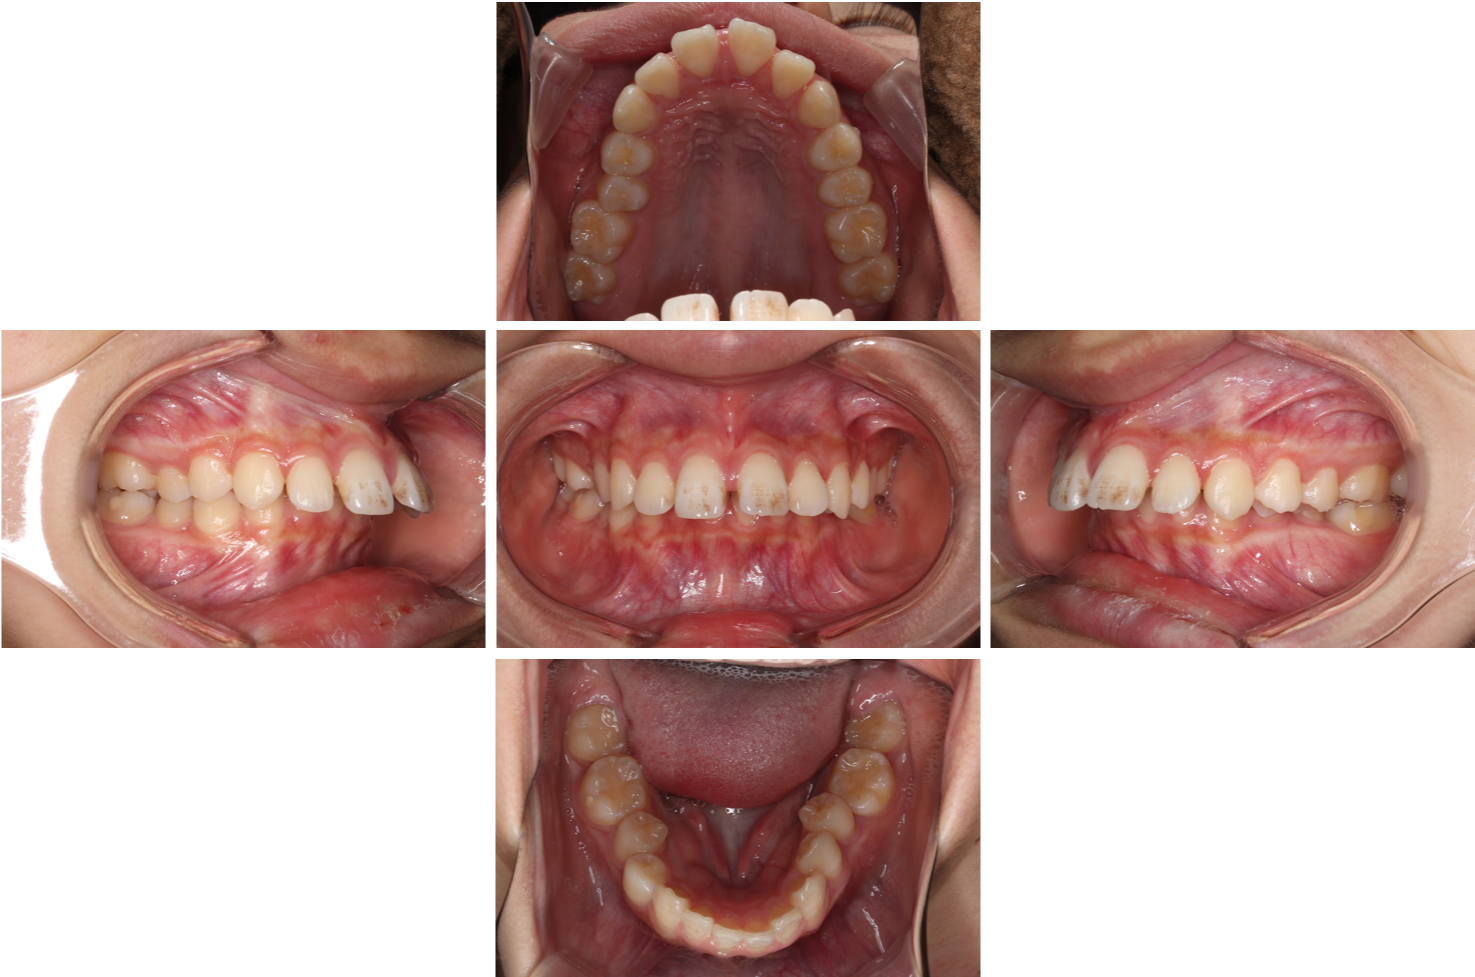

初診時

| ■診断名 | 著しい過蓋咬合を伴う骨格性上顎前突症 |

| ■初診時年齢 | 16歳1ヶ月 |